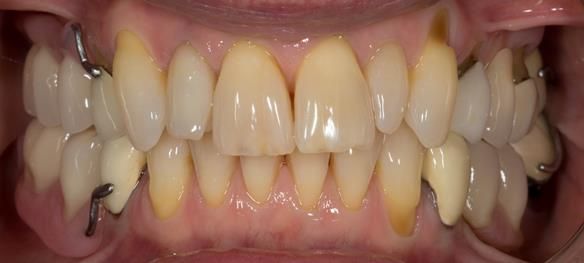

This newsletter describes in step by step detail Angela's transition through immediate partial dentures to crown supported definitive metal based dentures.

This 58 year old woman was referred to me by her general dental practitoner for treatment.

- Generalised Periodontitis; Stage 4, Grade C, Currently Unstable. Risk Factors: Type 1 diabetes. 16, 17 - hopeless prognosis. 14, 24, 26, 27, 34, 37, 44 - guarded prognosis

- Poor marginal fit and poor appearance of crowns and bridgework

- Yellowing teeth

The clinical situation and treatment process is shown in detail below with photographs. I (Finlay Sutton) provided the clinical work and Rowan Garstang provided the technical work.